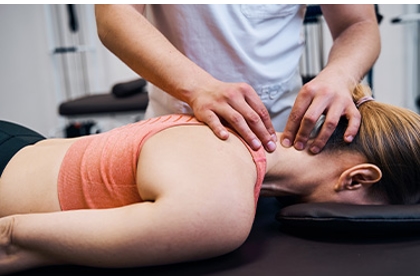

Pain is your body’s way of alerting you to a problem. At Bidwell Chiropractic, our team’s goal is to discover, address, and treat those problems, often with spinal misalignments and adjunctive therapies. By using these treatments, we encourage the body’s natural healing abilities while at the same time restoring your comfort, mobility, and function. Whether you are suffering from back pain, stress, sleep problems, or something else, our knowledgeable staff can help you with safe, natural, drugless healthcare.

Our Moorestown, NJ chiropractic clinic is led by Dr. Sylvia Bidwell, and our staff is dedicated to practicing conservative, nonsurgical solutions to prevent and relieve pain. Our passion is to help your body heal itself through these high-quality chiropractic treatments. Dr. Bidwell understands how your back pain can make your everyday tasks more burdensome than ever, and that’s why she will take the time to listen to your story, your struggles, and what you are looking to achieve through chiropractic sessions.

Our chiropractic services help patients of all ages, including spinal decompression, spinal manipulation and adjustment, stretching and strengthening exercises, prenatal chiropractic, and pediatric chiropractic. Dr. Bidwell has extensive experience using chiropractic to help patients recover from auto injuries, as well, and encourages patients to come in for a consultation whether they are currently experiencing pain or are taking proactive steps to address spinal and whole-body wellness.

Chiropractic care is an excellent way to address pain without resorting to more invasive treatment strategies like drugs or surgery. Instead, chiropractors like Dr. Bidwell emphasize the importance of helping the body’s natural ability to heal itself through spinal adjustments and adjunctive therapies, as well as helping provide advice for “homework” you can practice outside of our clinic, such as better nutrition, sleep advice, improved posture, and making your workplace more ergonomic.